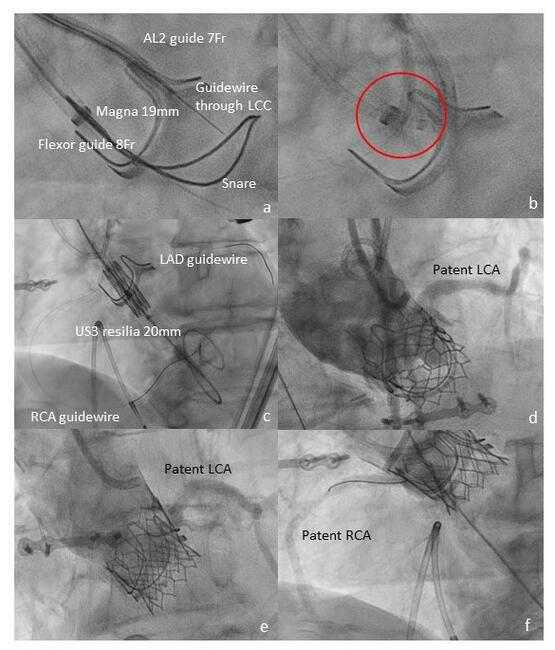

BASILICA With Adjunctive Coronary Protection Enabling Valve-in-Valve Transcatheter Aortic Valve Implantation

Video Supplement to "BASILICA With Adjunctive Coronary Protection Enabling Valve-in-Valve Transcatheter Aortic Valve Implantation" (Clinical Image).